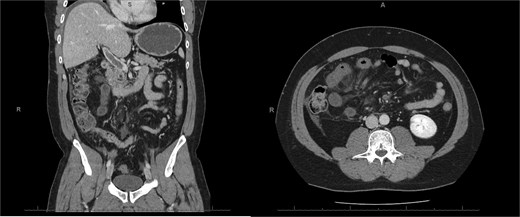

A 45-year-old male presenting with a 10-day history of isolated right lower quadrant (RLQ) abdominal pain. His history included deep vein thrombosis, coronary artery disease with prior STEMI, left anterior descending artery stenting in 2014, and ongoing antiplatelet therapy with aspirin. Upon admission, RLG tenderness was noted. Laboratory revealed leucocytosis (WBC 16 G/L) and elevated CRP (70 mg/L). E-CT revealed superior mesenteric and portal systems thrombosis with ischemia of a small bowel loop in the RLQ, characterized by absent bowel wall enhancement and free fluid (Fig. 4). Besides these findings, he was managed conservatively with a UFH bolus of 5000 U/l, followed by a continuous infusion of 36 000 U/l over 24 h (target INR 0. 35–0. 7), Ceftriaxone and Metronidazole, bowel rest, and ICU monitoring for 48 h. Clinical and biological improvement was rapid. E-CT on the second day showed no signs of perforation (Fig. 5). He was discharged after 7 days on LMWH (enoxaparin sodium 90 mg every 12 h). Twenty days later, he re-presented with acute RLQ pain and localized peritonism. E-CT revealed a covered perforation of the previously ischemic small bowel loop (Fig. 6). A segmental bowel resection with primary anastomosis was performed by laparotomy (Fig. 7). The postoperative course was uneventful, and he was discharged on postoperative day 4 with sodium enoxaparin 90 mg/12 h.

E-CT in the second patient at admission. White arrows showing porto-mesenteric thrombosis. Dashed arrows indicate a portion of small bowel loop ischemia in the right lower quadrant characterized by the absence of bowel wall enhancement and free fluid.